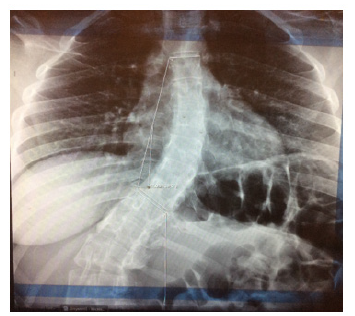

Patient M.B., 30 years old, entered the St. Petersburg City Orthopedic Center “Standart-Ortho”(chief of Deputy P. P. Peev) for routine orthosis. A history of poliomyelitis suffered in childhood, which resulted in a sharp cavitation of the spine (S-shaped spine scoliosis), deformation of the hip joints, flaccid paralysis of the legs, non-stable wearing of the knee joints, shortening of the left lower limb by 5 cm (Figure 1-3). Before prosthetics, the patient underwent surgical treatment-corrective operations on both legs: femur, tibia and feet bones.